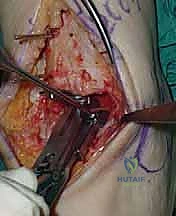

6. القطع العظمي الكاحلي (Talar Bone Cut)

بشكل مشابه، يتم توجيه دليل القطع نحو عظمة الكاحل (Talus) وإزالة السطح الغضروفي التالف وت

4. وضع أدلة القطع (Jig Placement and Alignment)

تعتمد دقة الجراحة على المحاذاة الصحيحة. يتم استخدام أجهزة توجيه متطورة (Jigs) تثبت على عظمة الساق باستخدام دبابيس معدنية. يتم التحقق من صحة الزوايا والمحاور باستخدام جهاز الأشعة السينية المباشر داخل غرفة العمليات (C-arm Fluoroscopy). يضمن الدكتور هطيف أن يكون القطع موازياً للأرض تماماً عند وقوف المريض.